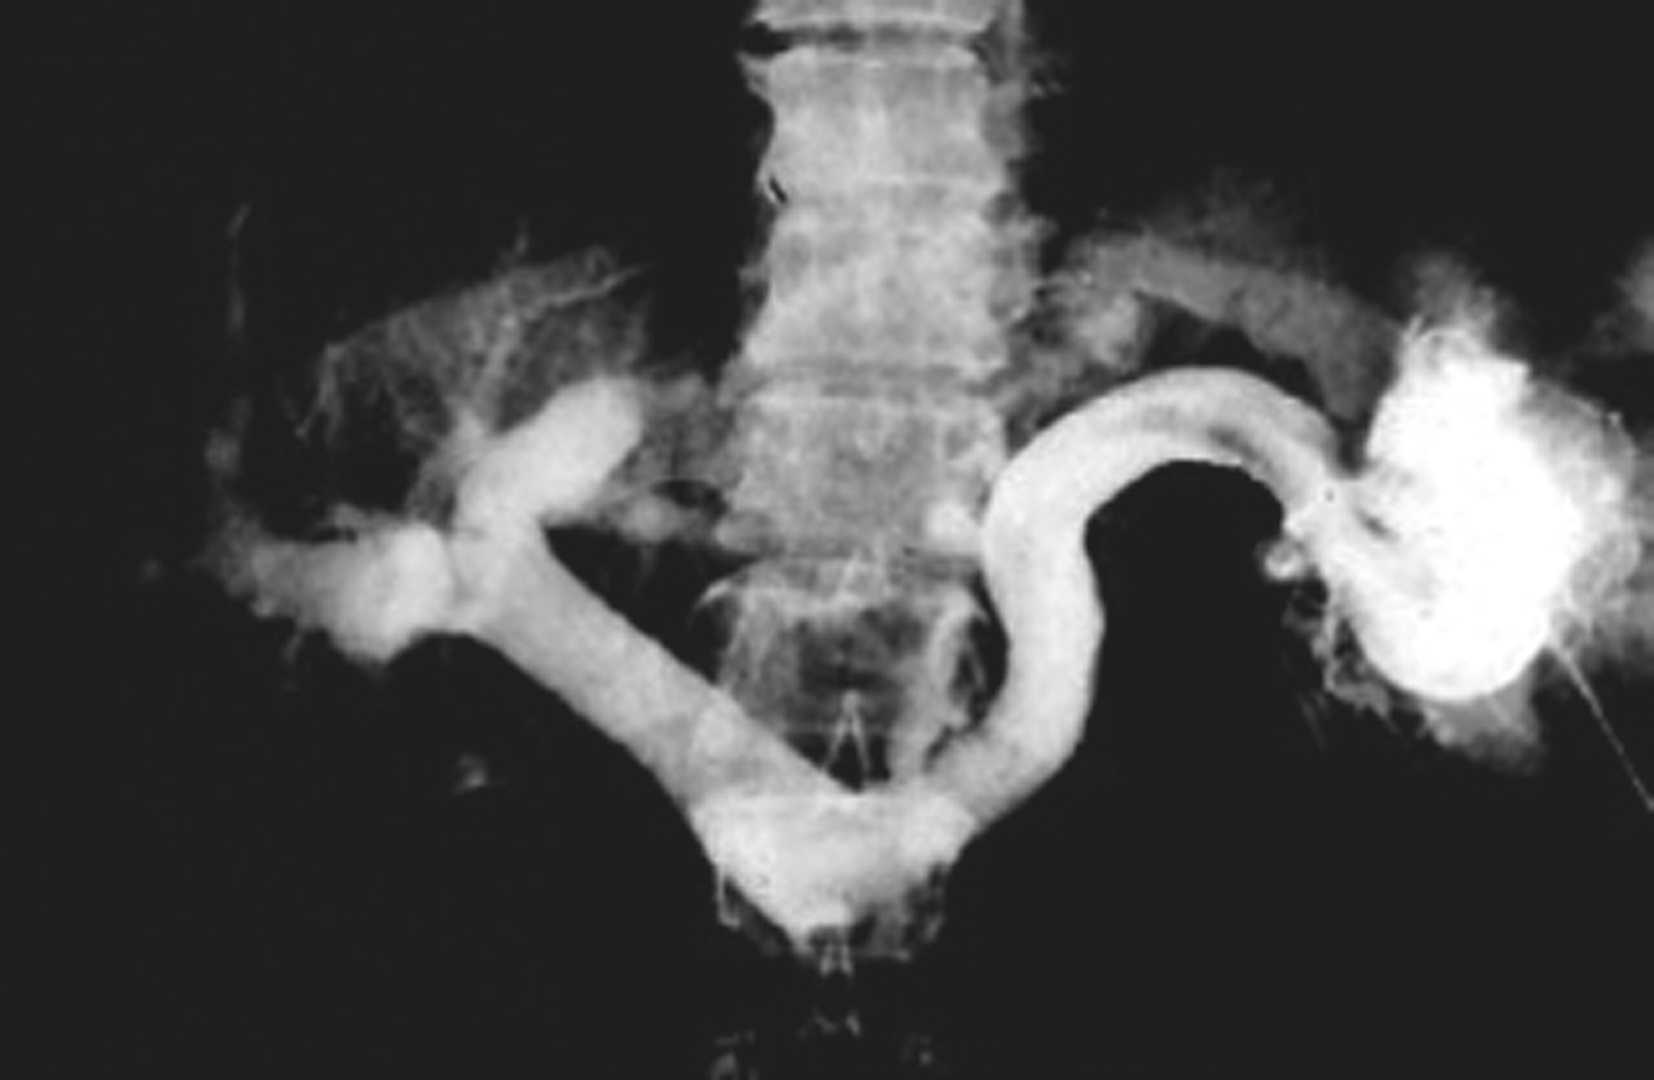

对比剂进入并显示门脉系统的形态分布,包括:门脉属支(肠系膜上、下静脉和脾静脉及其分支)、门脉干和门脉的分支(门脉左支和右支及其分支),同时可以观察门脉血流动力学状况。门脉造影可以为门脉相关疾病的诊断提供依据,也为经门脉的治疗提供解剖学基础和途径。根据对比剂进入门脉的方法不同,可有以下3种途径:

间接门脉造影即插管入脾动脉和/或肠系膜上动脉后,注入4~5mL/s,总量25~30mL造影剂,延长观察时间,不仅观察动脉期和实质期,还要观察对比剂回流后显示的门静脉期(图5-21-51)。间接门脉造影的操作相对简单,但通过对比剂的回流显示门脉,可受门脉循环时间和对比剂量的影响,且无法用来测量门脉压力。

图5-21-51 经肠系膜上动脉间接门脉造影

A.插管入肠系膜上动脉注入造影剂;B.经肠系膜上静脉回流后,可显示肠系膜上静脉、门脉干和门脉的分支

直接门脉造影即通过穿刺插管进入门脉的属支或门脉干,然后注入对比剂,造影观察门脉系统的情况和门脉血流动力学,可作为诊断门脉病变的“金标准”,也可作为门脉系统病变的治疗途径。其入路有:①经皮肝途径。多首选经右腋中线附近,采用21~22g的穿刺针穿刺门脉的右支及其2~3级分支,成功后引入导管进入门脉干。困难时,亦可选择经剑突下穿刺门脉左支及其分支(图5-21-52)。②经左腋中线附近采用21~22g的穿刺针穿刺脾静脉分支,然后插管进入门脉干(图5-21-53)。③经颈静脉,采用特殊的穿刺针经肝静脉穿刺肝内门脉分支[transjugular intrahepatic portosystemic stent-shunt(TIPSS)途径,图5-21-54]。④其他少用途径。如通过外科手术的方法,分离出肠系膜上静脉的分支,然后直视下插管入门脉等。常用的是经皮肝入路。穿刺可以在超声或(结合)透视引导下完成。门脉插管成功后,可注入适量的对比剂,行门脉DSA,显示门脉的情况,同时可经导管测量门脉的压力。采用导管导丝技术,可行超选择性插管进入门脉的属支或者门脉的分支内,同时可造影和测压。本法虽有一定的创伤,但是诊断门脉病变的“金标准”。其适应证为:①观察门脉系统,包括:门脉属支、门脉干及其分支血管的病变和解剖变异,如门静脉瘤、门静脉狭窄或闭塞、门静脉侧支循环的开放和门静脉海绵样变等。②为门静脉高压的诊断提供证据。测量门静脉压力持续升高(>10mmHg),即为门静脉高压。③为经门静脉的治疗建立了途径。如肝恶性肿瘤区域门静脉的栓塞以促进正常肝的代偿,出血门静脉分支的栓塞,建立肝内门静脉和腔静脉的分流道(TIPSS)以降低门脉压等。其禁忌证是相对的,主要是出凝血功能严重障碍和肾功能衰竭。门脉系统慢性完全性闭塞并血管成条索状改变,可能导致门脉穿刺插管失败。本法的并发症主要来源于穿刺插管途径的损伤造成的出血,栓塞造成的门脉血栓形成等。采用有效的方法准确的栓塞肝内的穿刺入路,可减少出血的发生,如用明胶海绵条、钢圈和组织胶等。穿刺过程中损伤肝动脉的分支亦是术后出血的原因之一,必要时行肝动脉造影明确和行栓塞术。

图5-21-52 经皮肝途径门脉造影

经皮肝穿刺门脉干成功后,引入导管,造影显示脾静脉、肠系膜下静脉和门脉干及其分支。并行钢圈栓塞胃冠状静脉